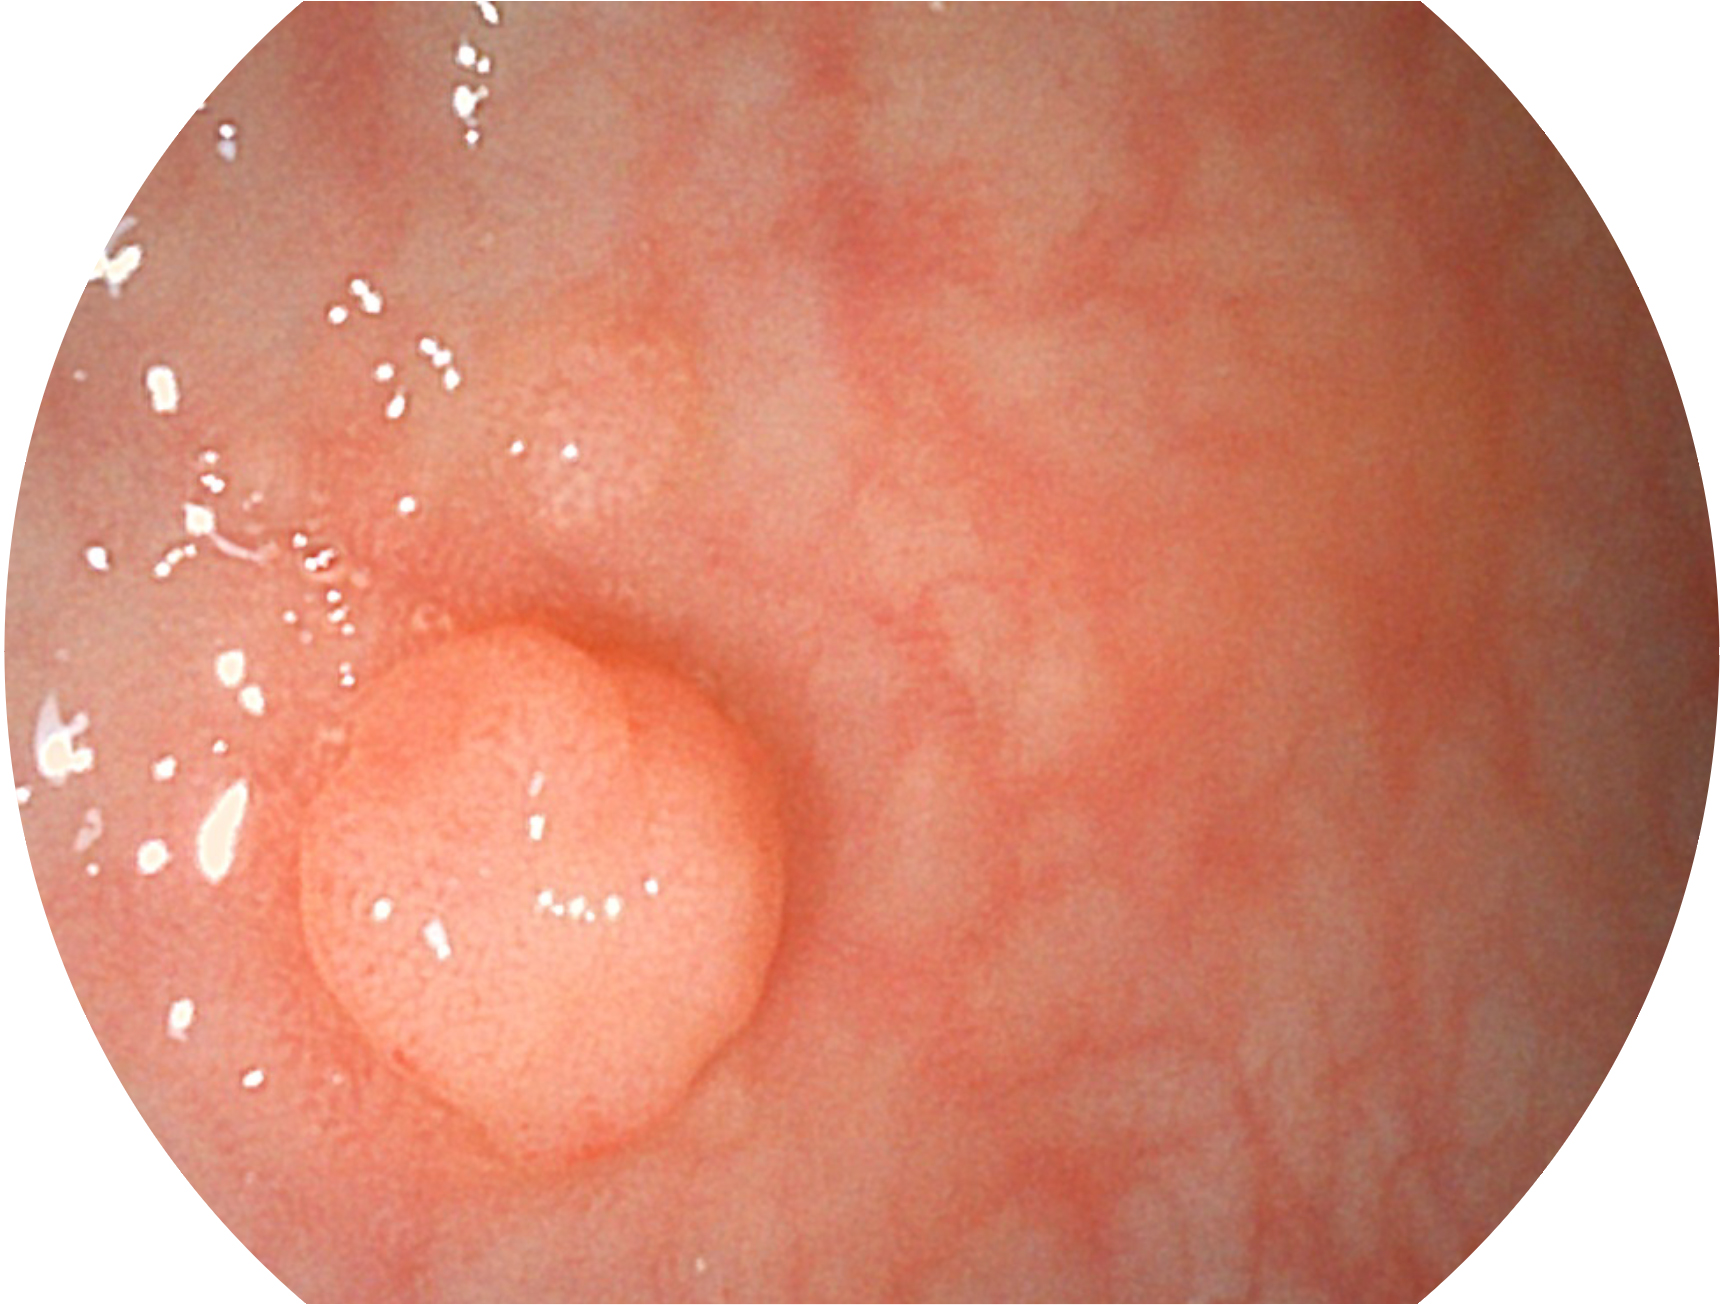

• 白光圖像 VIST圖像